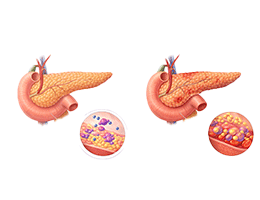

당뇨병 (Diabetes Mellitus)

고지혈증 (Hyperlipidemia)